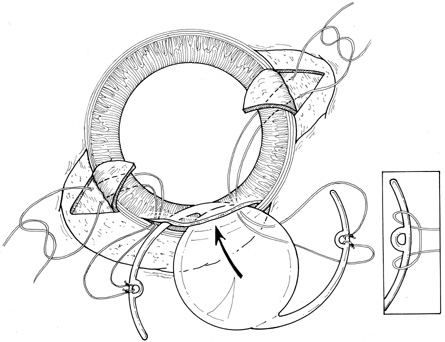

I recently found a very knowledgible doctor who has evaluated my complicated eye condition & is confident he can perform the unique procedures. Medical technology at the time of my initial eye surgeries was less advanced, leaving the anatomy of my eyes as one more challenge today. Without getting into any gory details of this next surgery on April 29th, the plan is to secure a special, artificial, intraocular lens implant, as well as perform a pupilloplasty. I will most definitely need plenty of recovery time.

I recently found a very knowledgible doctor who has evaluated my complicated eye condition & is confident he can perform the unique procedures. Medical technology at the time of my initial eye surgeries was less advanced, leaving the anatomy of my eyes as one more challenge today. Without getting into any gory details of this next surgery on April 29th, the plan is to secure a special, artificial, intraocular lens implant, as well as perform a pupilloplasty. I will most definitely need plenty of recovery time.